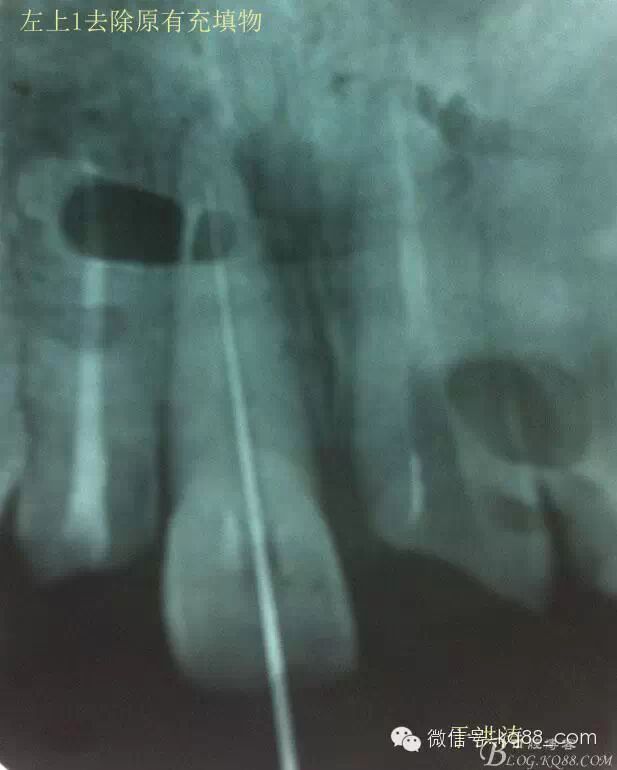

檢查:明顯可見22牙冠橫向斷裂至頸1/3處,近遠中與腭側斷裂至齦下??梢?/span>11牙冠斜向近中斷裂,近中與腭側均斷裂至齦下。21牙冠中1/3有裂痕。11 21 22松動(0),11 21叩(+),22叩(-),11 21 22探(-),11 21 22冷熱(-)。11 21 22唇側牙齦與粘膜和根尖相應部位未見明顯改變。11 22腭側牙齦增生性改變。11 21 22腭側粘膜和根尖相應部位未見改變。11 21 22舌側窩均有充填物。面部左右對稱無改變。余牙正常。(11,21,22牙冠顏色無改變)。 輔助檢查:X線片檢查11 22牙冠均有缺失。11 21 22 髓腔內均有充填物,11充填不到位, 21充填不實,22充填到位髓腔高密度影像。11 21 牙周膜有增寬,21根尖區(qū)有2mm左右低密度影像。未發(fā)現(xiàn)有牙根側穿或斷裂異物。 診斷:11,21慢性尖周炎,11,22殘冠。 治療計劃: 22無需治療。11 21 建議牙齒根管再治療。告知情況及費用。 1,11 21去除根充物。 2,11 21根管治療。 3,11 22纖維樁樹脂核修復。 4,高頻電刀去除11 22腭側牙齦組織到斷面。 5,11,21,22全瓷單冠修復牙齒。 治療過程:經(jīng)患者同意。H銼去除11 21原有充填物,未發(fā)現(xiàn)明顯滲出物,無異味。K銼疏通根管,VDW根測儀測量長度,11牙20mmWL,21牙20mmWL。S3鎳鈦器械預備根管。(全程1%次氯酸鈉沖洗EDTA溶解潤滑)試尖片顯示牙膠未到位,繼續(xù)向牙根尖各2mm進入預備。吸潮紙尖吸干根管,登士柏樹脂根充糊劑輸送至根尖部位,以測量數(shù)據(jù)用牙膠尖冷充側壓充填根管,3M玻璃離子封閉根管口。不可用患牙啃咬硬物,擇日冠修復。 輔助檢查:插針X線片顯示根管內充填物已經(jīng)取出。試尖片顯示牙膠尖未到位,繼續(xù)用K銼和機括向根尖預備。根充結束片顯示根充密實,無超充,無欠充。 醫(yī)囑:常規(guī)醫(yī)囑,不適隨診。 各步驟操作見下圖 于洪濤 2015.02.03 復 診 主訴:無疼痛,不適癥狀已經(jīng)消失。 檢查:11 21 充填物存在邊緣封閉完好,叩(-)松動(0)牙齦及周圍同初診。11 21 22無任何不適。 治療過程:由于患者自身原因即將兩個月來復診。拍X線片,去除11 22髓腔內部分牙膠,P鉆預備根管到達預定位置。粘結纖維樁,制作冠核。初預備11 21 22牙冠。高頻電刀按廠家要求功率和方法去除11 22腭側牙齦組織到達牙齒斷裂部位,調整檔位和功率繼續(xù)凝固和精修腭側組織,11 21 22排齦精修拋光。硅橡膠兩次法取模,可見模型完整肩臺清晰。制作臨時冠,科爾不含丁香油臨時冠粘結系統(tǒng)粘接。 模型送技師制作。預約義齒佩戴時間。(需術前牙齒比色) 輔助檢查:X線片顯示根尖低密度影像消失,牙周未見異常。X線片顯示纖維樁密合到位。 醫(yī)囑:不可用臨時牙肯咬硬物,不適隨診。 各步驟操作見下圖 于洪濤 2015.03.26 復 診 主訴:牙齒無癥狀,自感腭側術區(qū)舌舔粘膜不適。 檢查:臨時冠完整,無松動,邊緣緊密。牙齒無疼痛,唇側牙齦無明顯紅腫,腭側牙齦愈合良好,牙冠肩臺邊緣清晰。腭側牙齦術區(qū)中度觸及有少量滲血。 治療過程:義齒制作完成。去除臨時冠及粘結物。義齒試戴調整完全就位,無懸突,無縫隙。清洗義齒,氫氟酸處理義齒50秒(加強醫(yī)患防護),沖洗吹干,偶聯(lián)劑處理備用。基牙37%酸處理15秒,沖洗吹干,隔濕,排齦,涂第五代粘結劑。小蜜蜂雙固化樹脂水門汀激活攪拌注入義齒中,按順序就位,加壓力,牙線去除牙縫隙多余樹脂,涂阻氧劑,基牙唇腭側各光照固化3秒之后去除多余水門汀取出排齦線,繼續(xù)光照固化牙齒每個面20秒。精細查找去除多余水門汀。 醫(yī)囑:1,患牙咀嚼硬物加以注意。 2,常規(guī)醫(yī)囑,不適隨診,。 3,加強口腔衛(wèi)生意識。定期復診檢查。 各步驟操作見下圖 于洪濤 2015.04.07 回訪病例 主訴:咀嚼食物非常自如,無任何不適。 檢查:義齒牙體完整。無松動,無叩痛。唇側牙齦紅潤質韌無萎縮,腭側術區(qū)牙齦愈合良好,無炎癥改變。唇腭側根尖相應部組織無改變。余牙正常。 輔助檢查:X線片顯示牙根及周圍未見異常。未見骨萎縮。牙冠及頸部未見異常。 醫(yī)囑:定期檢查義齒,不適隨診。 各步驟操作見下圖 于洪濤2015.04.28